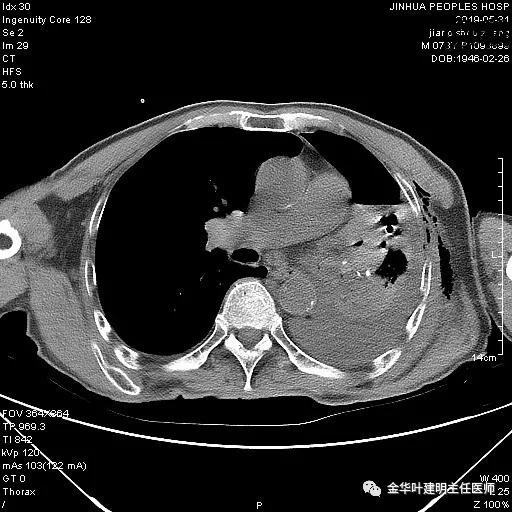

6.4上午:24小时引流出血性乳糜液1800毫升。是否再次手术进行右进胸胸导管结扎,抑或继续保守治疗非常纠结!压力非常大!!多方讨论会诊无法取得一致意见,但一般认为,引流量在1000毫升以上宜积极手术。情况与浙二医院范军强教授联系,请求指导,范教授认为左侧肺手术,损伤胸导管主干的机会较小,多数可保守治疗而愈。在他们的病例中,也有结扎胸导管后引流量仍无减少,效果并不能完全保证。建议可以考虑胸管夹管观察(因为淋巴管压力低,予以适当的压力,漏出量可能会明显减少),同时继续禁食,并静脉营养支持,引流管口可能会有渗液,注意更换敷料。与家属充分沟通后决定试夹管;这天血色素9.0 g/L;胸部CT复查示: